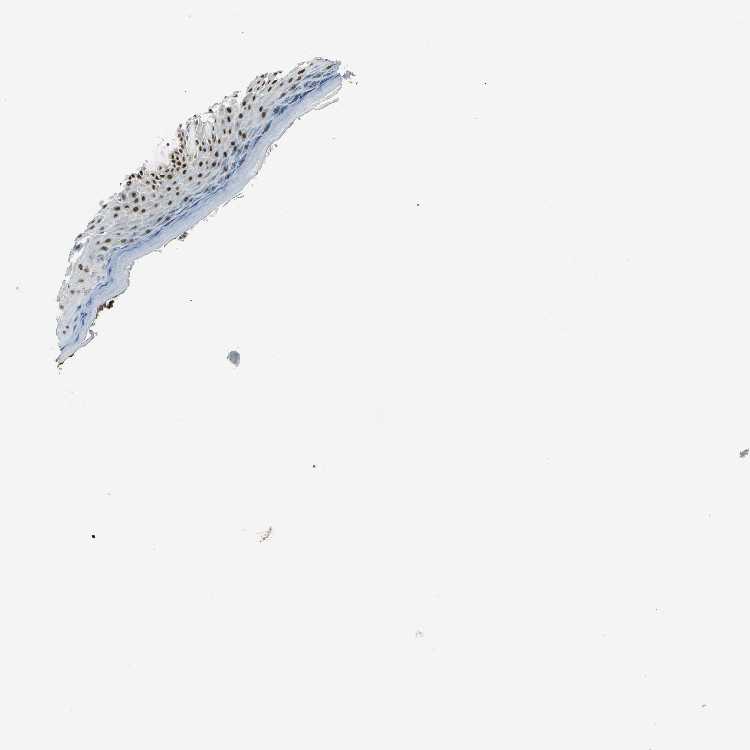

SKIN 1 - Antibody stainingi

Antibody staining in the annotated cell types in the current human tissue is reported as not detected, low, medium, or high, based on conventional immunohistochemistry profiling in selected tissues. This score is based on the combination of the staining intensity and fraction of stained cells.

Each image is clickable and will lead to virtual microscopy that enables deeper exploration of all samples and also displays staining intensity scores, fraction scores and subcellular localization as well as patient and tissue information for each sample.

Antibody HPA006111Antibody HPA008884

Langerhans High-

Cells in basal layer -Medium

Cells in corneal layer -Not detected

Cells in granular layer -Low

Cells in spinous layer -Medium

Endothelial cells -High

Extracellular matrix -Not detected

Fibroblasts Medium-

Fibrohistiocytic cells -High

Keratinocytes High-

Langerhans cells -Medium

Lymphocytes -High

Melanocytes Not detectedMedium